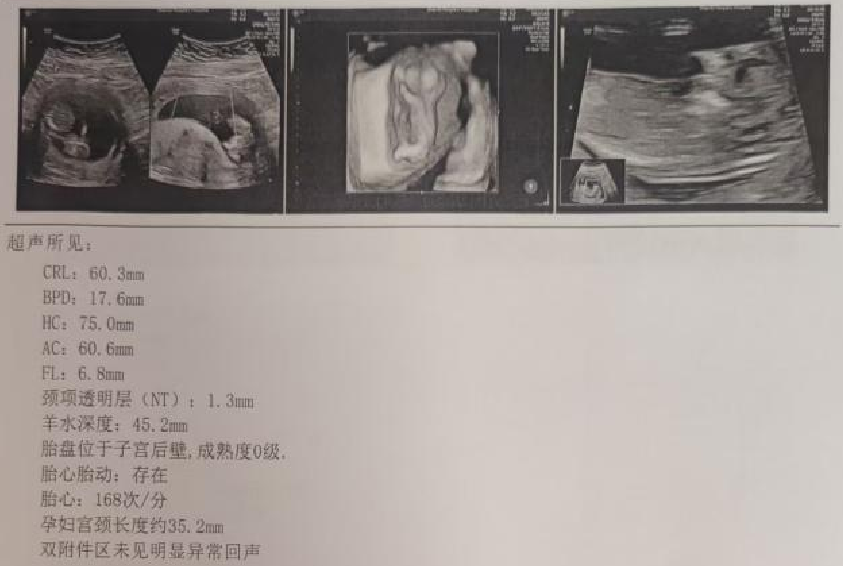

超声检查(孕12周):

宫内镜怎么进入子宫【素手琴心专场】王素琴主任医师:妊娠期子宫蜕膜息肉的阴道内镜处理策略及时机_https://www.jmylbn.com_新闻资讯_第6张